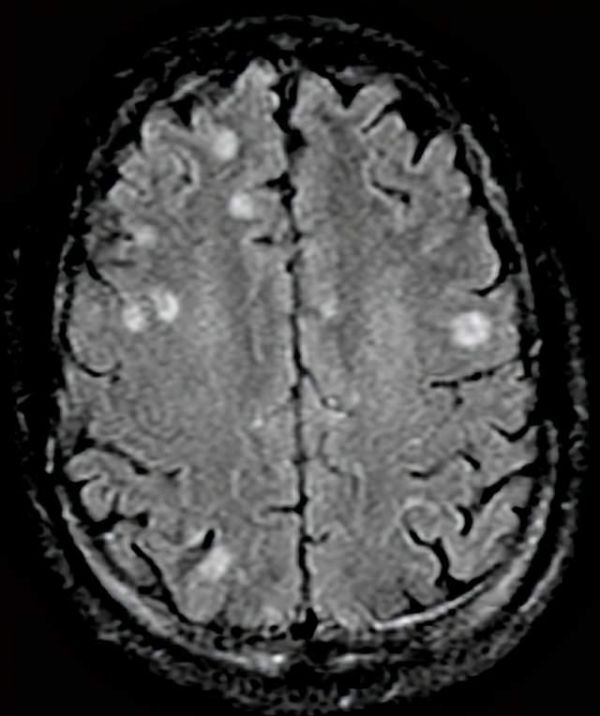

弓形虫在人脑内形成的囊肿(白色部位)丨来源:https://microbewiki.kenyon.edu/index.php/File:Oit_c3_d04.png